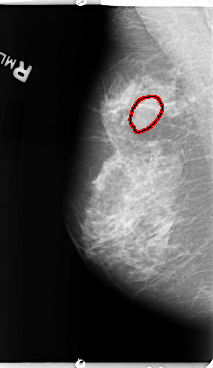

B_3116_1.RIGHT_CC

RIGHT_CC LINES 4704 PIXELS_PER_LINE 2416 BITS_PER_PIXEL 12 RESOLUTION 50 OVERLAY

FILE: B_3116_1.RIGHT_CC.OVERLAY

TOTAL_ABNORMALITIES 1

ABNORMALITY 1

LESION_TYPE MASS SHAPE N/A MARGINS ILL_DEFINED

ASSESSMENT 4

SUBTLETY 2

PATHOLOGY BENIGN

TOTAL_OUTLINES 1

BOUNDARY